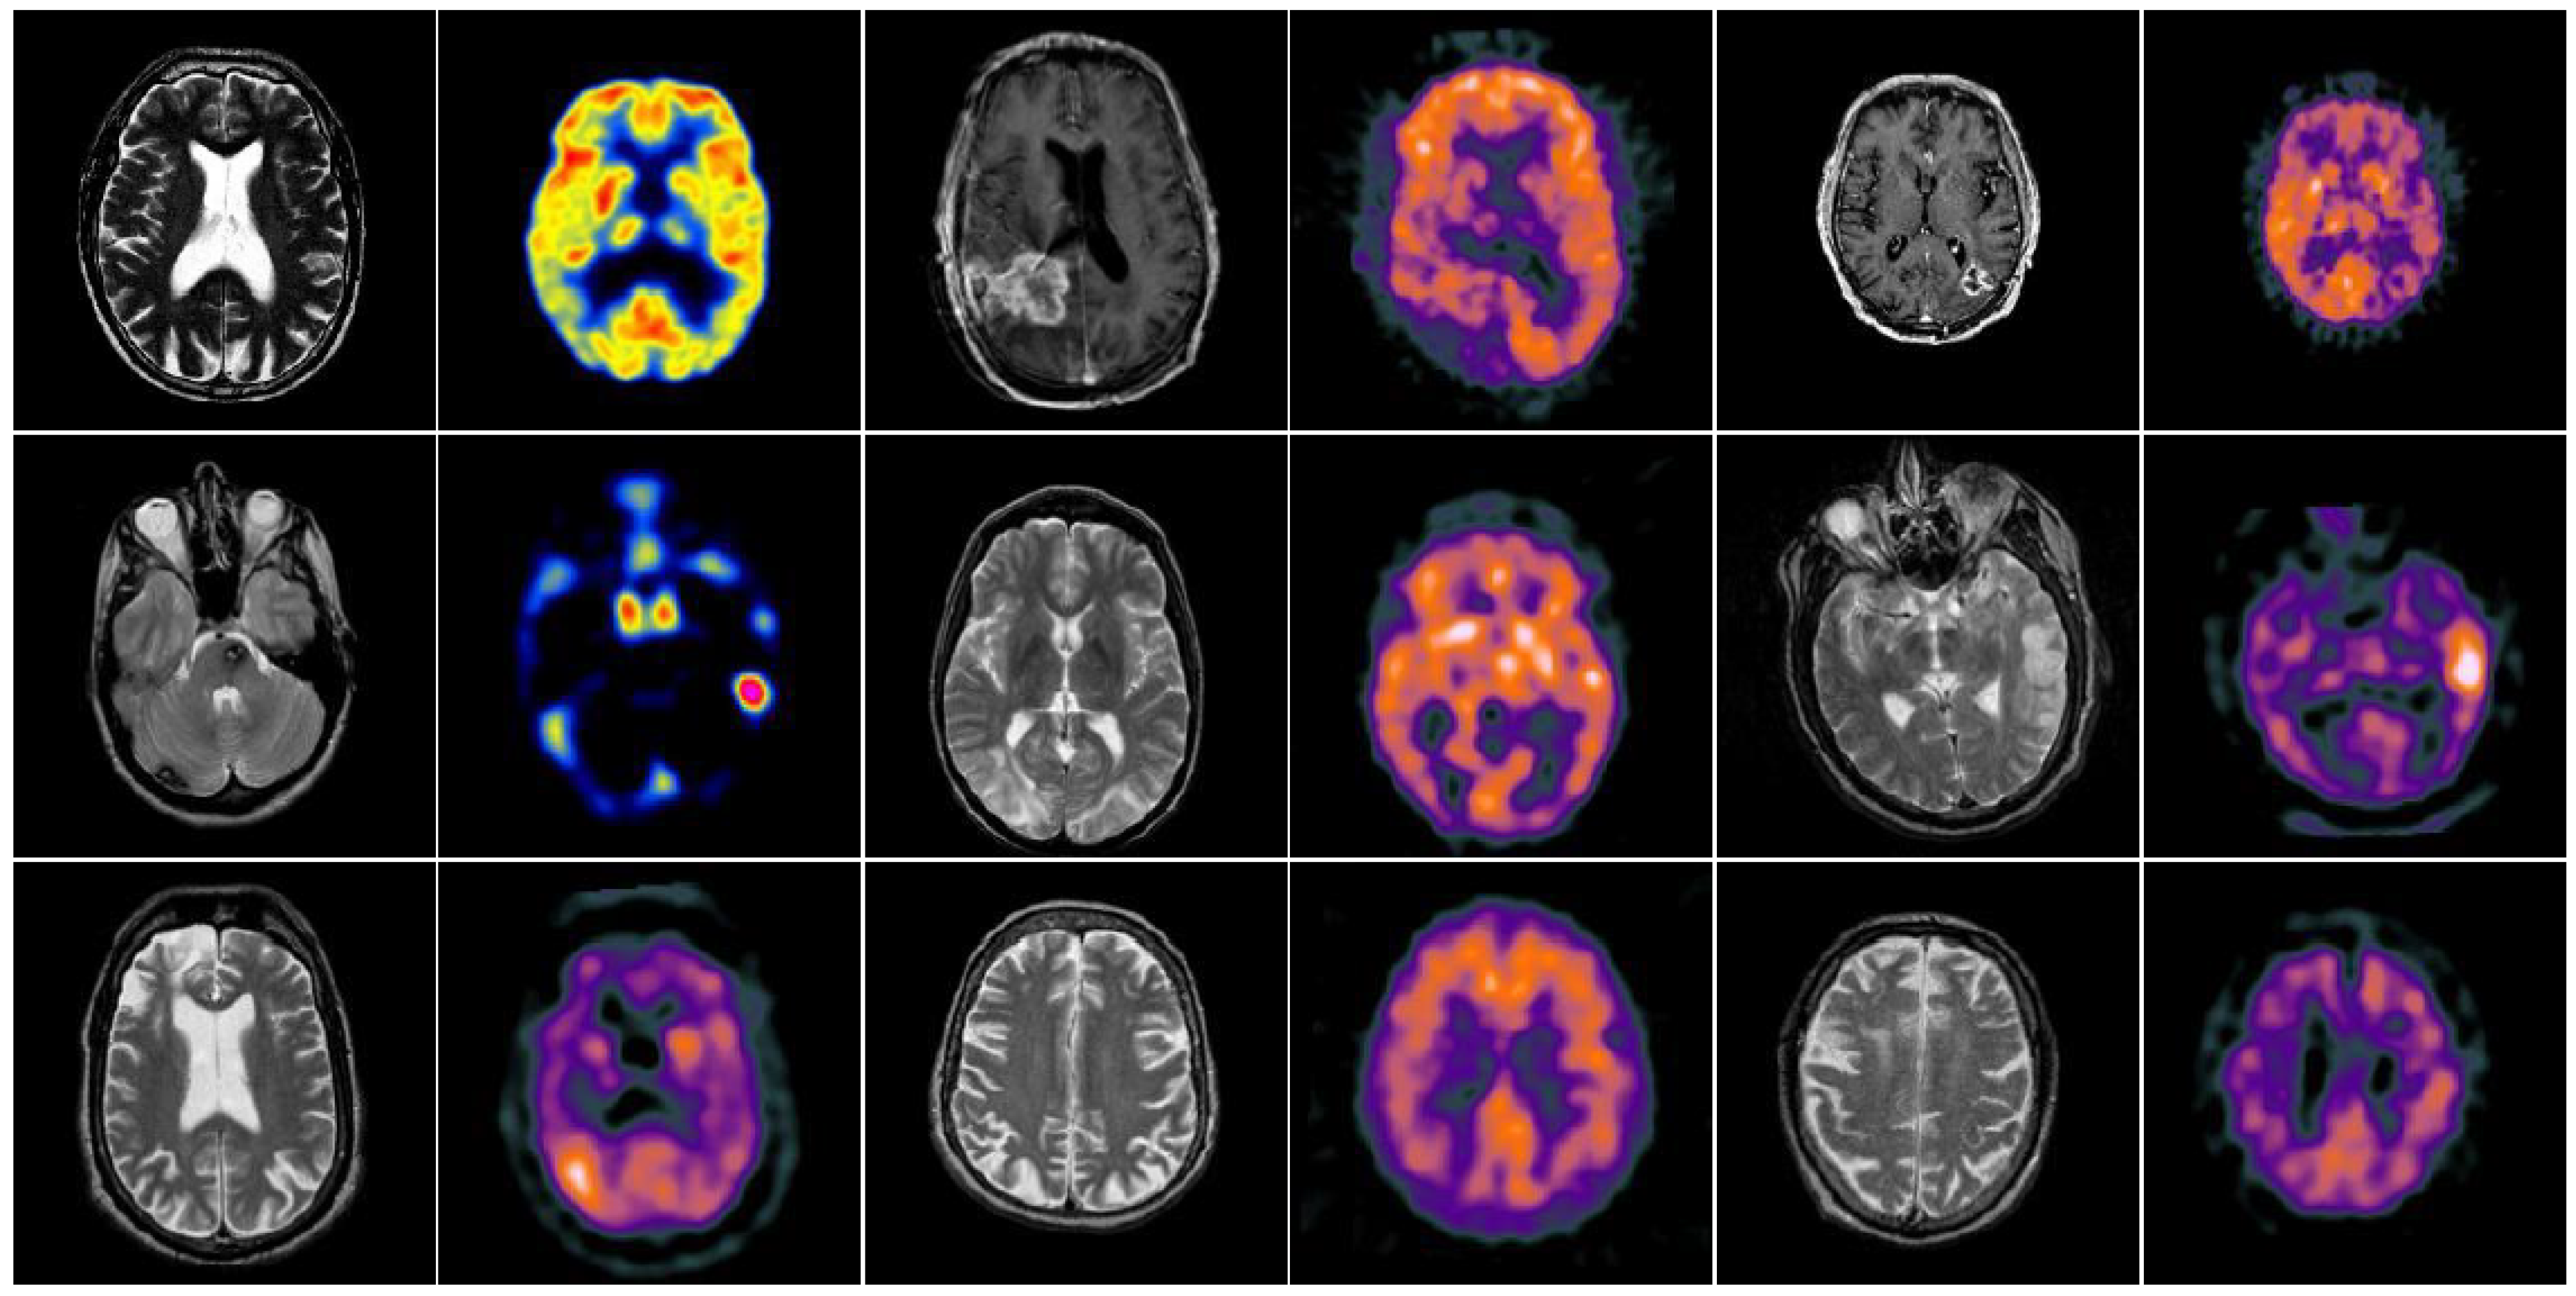

4.3. Comparison of Anatomical and Functional Image Fusion